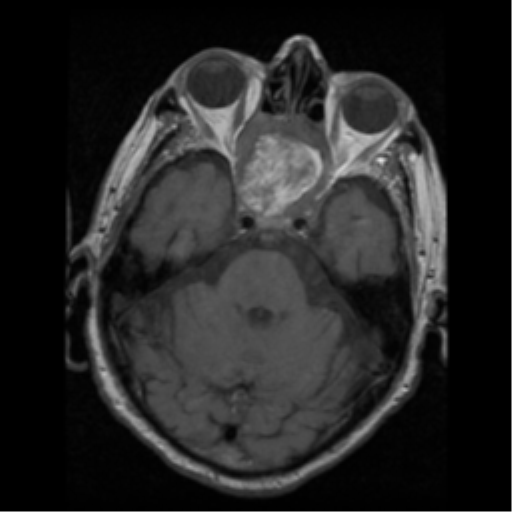

Ecchordosis Physaliphora

Cystic lesion in the prepontine cistern without enhancement or restricted diffusion extending into bone.

Absence of enhancement or restricted diffusion together with non-aggressive bony margins in this location is typical of a retroclival ecchordosis physaliphora, a notochord remnant.

Ecchordosis physaliphora is a congenital benign hamartomatous lesion derived from notochord remnants, usually located in the retroclival prepontine region, but can be found anywhere from the skull base to the sacrum.